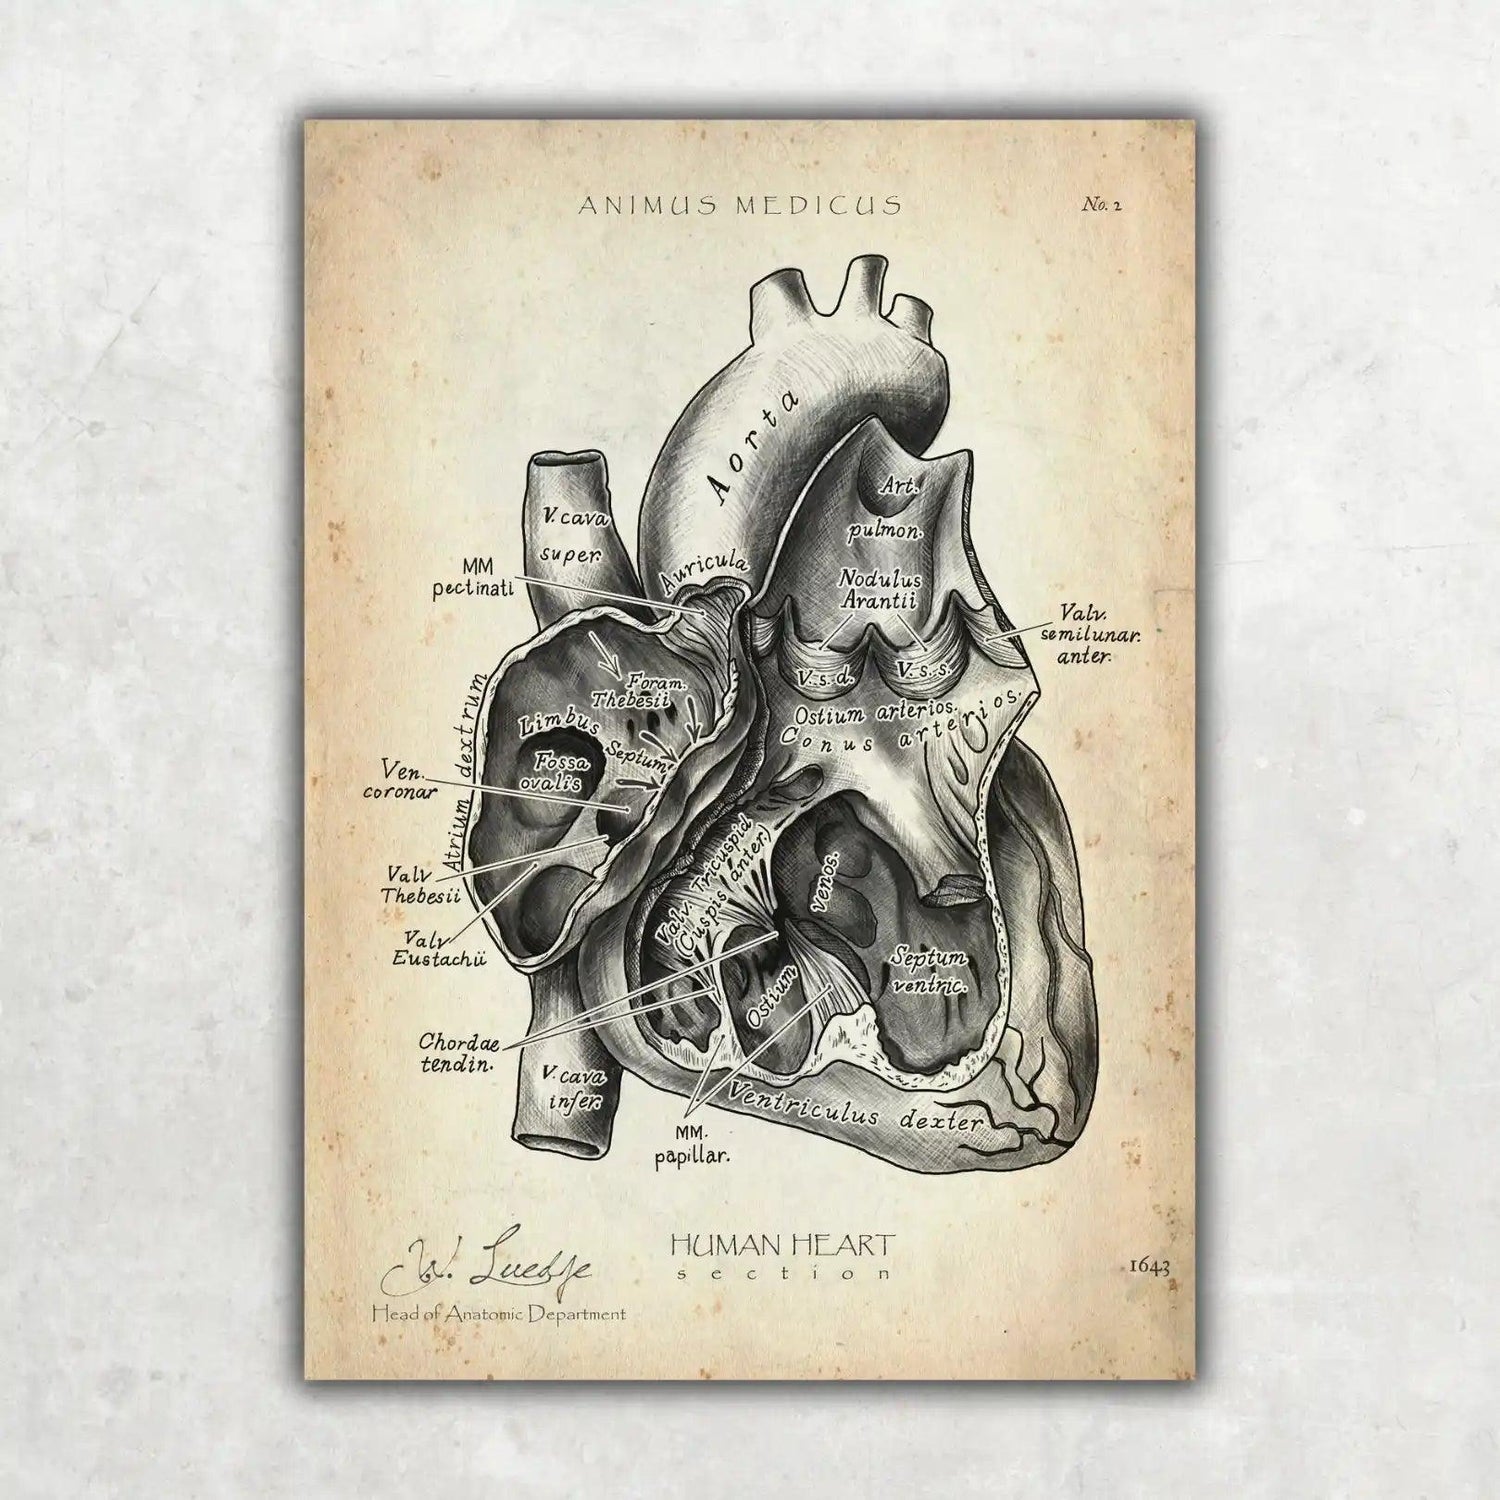

Warst du auf der Suche nach einer Möglichkeit, die faszinierende Anatomie des Herz-Kreislauf-Systems nicht nur zu lernen, sondern auch visuell zu erleben? Bei Animus Medicus findest du ästhetische Anatomie-Poster im Vintage-Stil, die medizinisches Wissen und kunstvolles Design perfekt vereinen. Entdecke jetzt unsere Kollektionen auf https://animus-medicus.de und bringe die Schönheit der Anatomie an deine Wände.